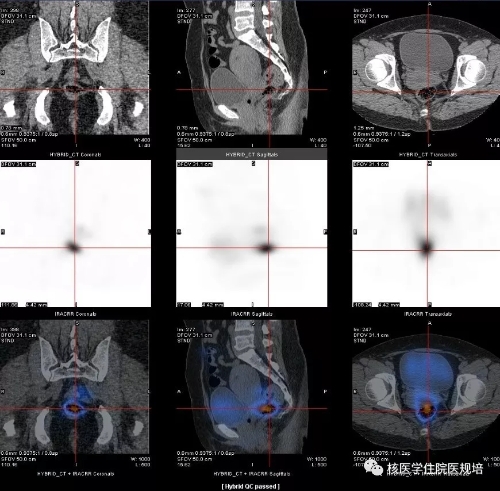

图2 盆腔SPECT/CT显像

口服131I5.55 GBq后3天行全身显像(图1),结果见:颈部甲状腺区域未见明显异常示踪剂浓集区;口鼻部及胃肠道可见生理性示踪剂摄取;盆腔内膀胱左上方可见一团片状不规则异常示踪剂浓集区,进一步行相应区域SPECT/CT后,见该浓聚灶位于乙状结肠,CT可见一由肠腔向外突出的囊袋影(图2)。全身其他部位未见明显异常显像剂摄取。

3.盆腔内131I浓聚灶考虑位乙状结肠憩室内滞留可能性大,建议进一步肠镜检查。

该患者于本次碘治疗后1月行肠镜检查,证实患有乙状结肠憩室(图3)。

本例女性患者,既往否认肠道疾病史,否认子宫肌瘤等妇科疾病史,围碘治疗期无便秘、腹痛等症状。该患者刺激性Tg并不达标,且首次治疗后刺激性Tg水平降低,131I Rx-WBS显示盆腔团块状异常示踪剂浓集区,并不能除外有功能性转移灶存在。因此临床并不能完全用生理性或异位摄取原因解释,进一步行腹部及盆部断层显像也是非常有必要的。盆腔断层显像显示乙状结肠憩室放射性滞留,放射性碘治疗后1月行肠镜检查证实为乙状结肠憩室,排除盆腔功能性转移性病灶,对患者诊断分期、治疗评价及后续治疗方案的确定有决定性意义。